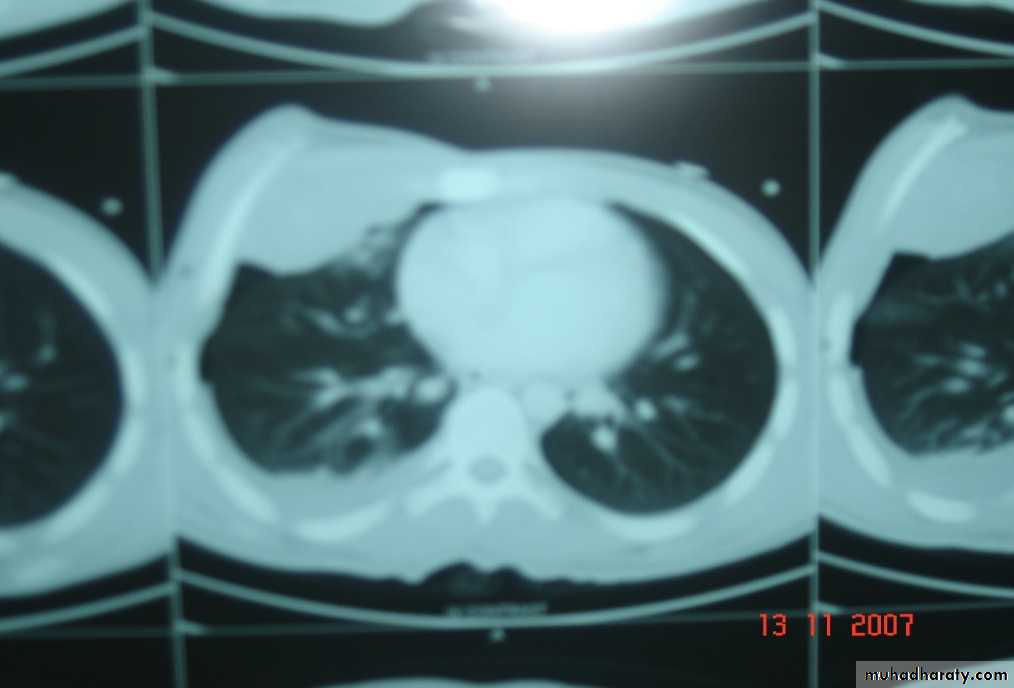

• Chest X-ray ,CT chest ..

• Pathology :-A-Central type is the commonest (75%).It arises in one of the main bronchi or their primary division leading to bronchial obstruction with secondary changes in the lung such as atelectasis .B-Peripheral type (25%) arises from the smaller bronchi and remains symptom less for long time .

Histologically Squamous cell Ca (SCC) 60% , smoker , centrally located ,metastasizes to mediastinal & supraclavicular LN . Adenocarcinoma (15% ) , located peripherally , more in women .Tends to metastasizes to the liver , brain ,bone & adrenals in addition to the LN Undifferentiated carcinoma (oat) cell carcinoma and large cell carcino(20-30%) which includes small ma Alveolar cell carcinoma , located peripherally ,metastasizes to the liver and adrenalsRecent classification..Non small & small cell carcinoma